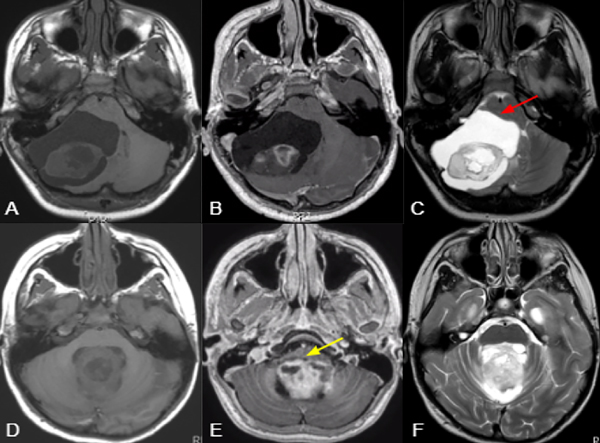

Figura 2. Cortes sagitales de RM de pacientes con APcs asociados a invasión troncoencefálica a distintos niveles: mesencefálica (A), pontina (B) y bulbar (C), con sus controles postoperatorios respectivos (E:G) señalando remanentes tumorales (flechas roja, verde y amarilla). La figura D demuestra una lesión predominantemente sólida y central que comprime pero no invade el tronco, la cual pudo ser completamente resecada (H).

El grado de resección se categorizó como resección total (RT), resección casi total (RCT), resección subtotal (RST) basada en la observación intraoperatoria del neurocirujano y RM con gadolinio postoperatoria analizada por especialistas en neuroimágenes (Figura 2). La RT correspondió a los casos en los que todos los hallazgos de imagen postoperatorios fueron negativos de acuerdo con la apreciación de los neurocirujanos. La RCT correspondió mayoritariamente a los casos en los que quedó un residuo tumoral mínimo < 2%, como en los casos de invasión del IV ventrículo, o cuando se consideró resección completa, pero aún se identificaron restos mínimos en la RM postoperatoria. RST, consecuentemente corresponde a  cualquier resección que no alcanzaba los criterios anteriores.

Se incluyeron un total de 100 pacientes con un seguimiento medio de 53,9 meses (rango 12-156). El 54% de la población analizada era de sexo femenino y la edad media fue de 7,6 años. La localización más frecuente fue la central (64%), y 29% de los casos correspondió a lesiones sólidas. El 24% de los tumores se asoció con invasión del tronco encefálico o de los pedúnculos cerebelosos (Figura 2).

La resección completa sigue siendo el pilar del tratamiento y el principal factor pronóstico en la SLP o recurrencia1,3,10. Cuando se documenta RT en la RMN postoperatoria, no hay necesidad de tratamiento adicional y la tasa de supervivencia general a los 10 años es mayor al  90 %1,9. Sin embargo, las tasas reportadas de RT oscilan entre el 50 y el 89 %, siendo la causa más significativa de RST la invasión del tronco encefálico1,3,4. En nuestra serie, reportamos una tasa de RT del 67% comprobada no solo por la técnica micro neuroquirúrgica, sino también por RMN postoperatoria, lo que reduce las falsas consideraciones. El 96 % de los pacientes que no alcanzaron la resección completa tenían afectación del tronco encefálico, demostrando el 24 % de los tumores invasión del tronco encefálico o de los pedúnculos cerebelosos, en correlación con los resultados de la resección incompleta (Figura 2).